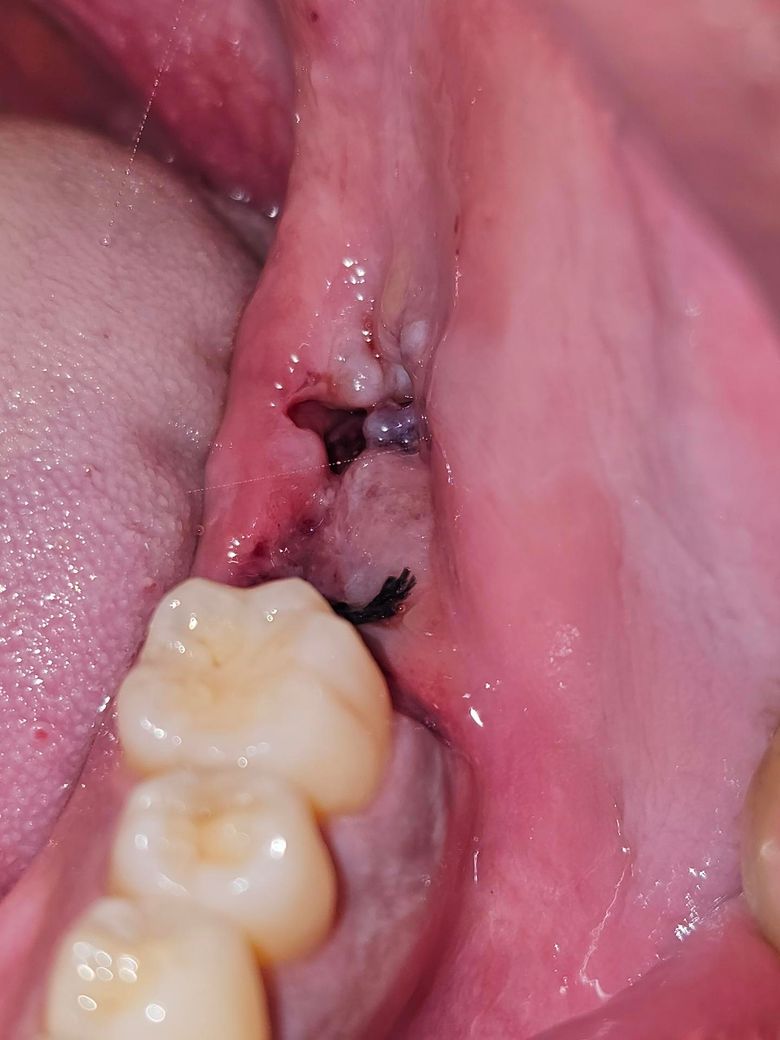

목요일에 어금니와 사랑니를 동시에 발치했고 오늘 모습입니다

어금니쪽은 혈병이 잘 보여서 치유 잘되는중이라는걸 알수 있는데 사랑니쪽이 애매하네요

사진으로 봤을 경우 문제가 없이 잘 아물고 있는 것으로 보입니다. 너무 걱정하지 않으셔도 될 것으로 생각되며 발치한 부위가 자극이 되지 않도록 하는 것이 좋습니다.